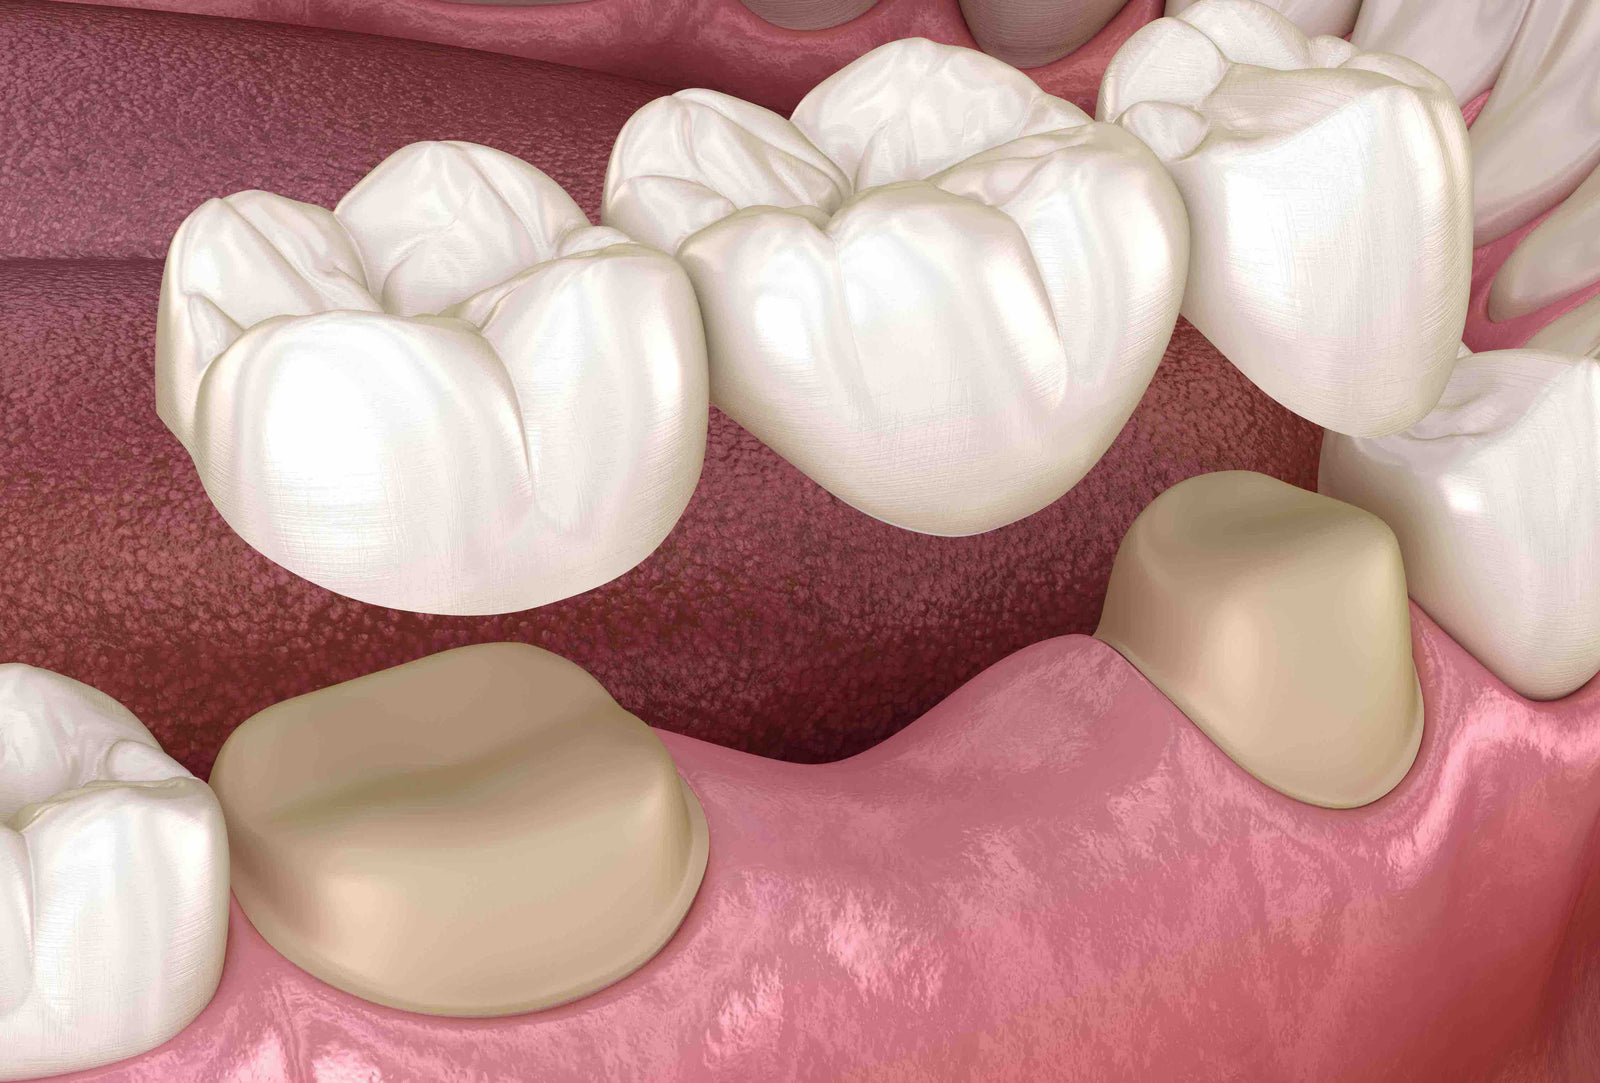

Lorsqu’il manque une ou plusieurs dents, et que le secteur est encadré par des dents couronnées ou nécessitant d’être couronnées, il est possible de souder sur ces dents une dent artificielle en suspension, qui ne repose ni sur l’os, ni sur la gencive. Cela permet d’éviter la pose d’un implant.